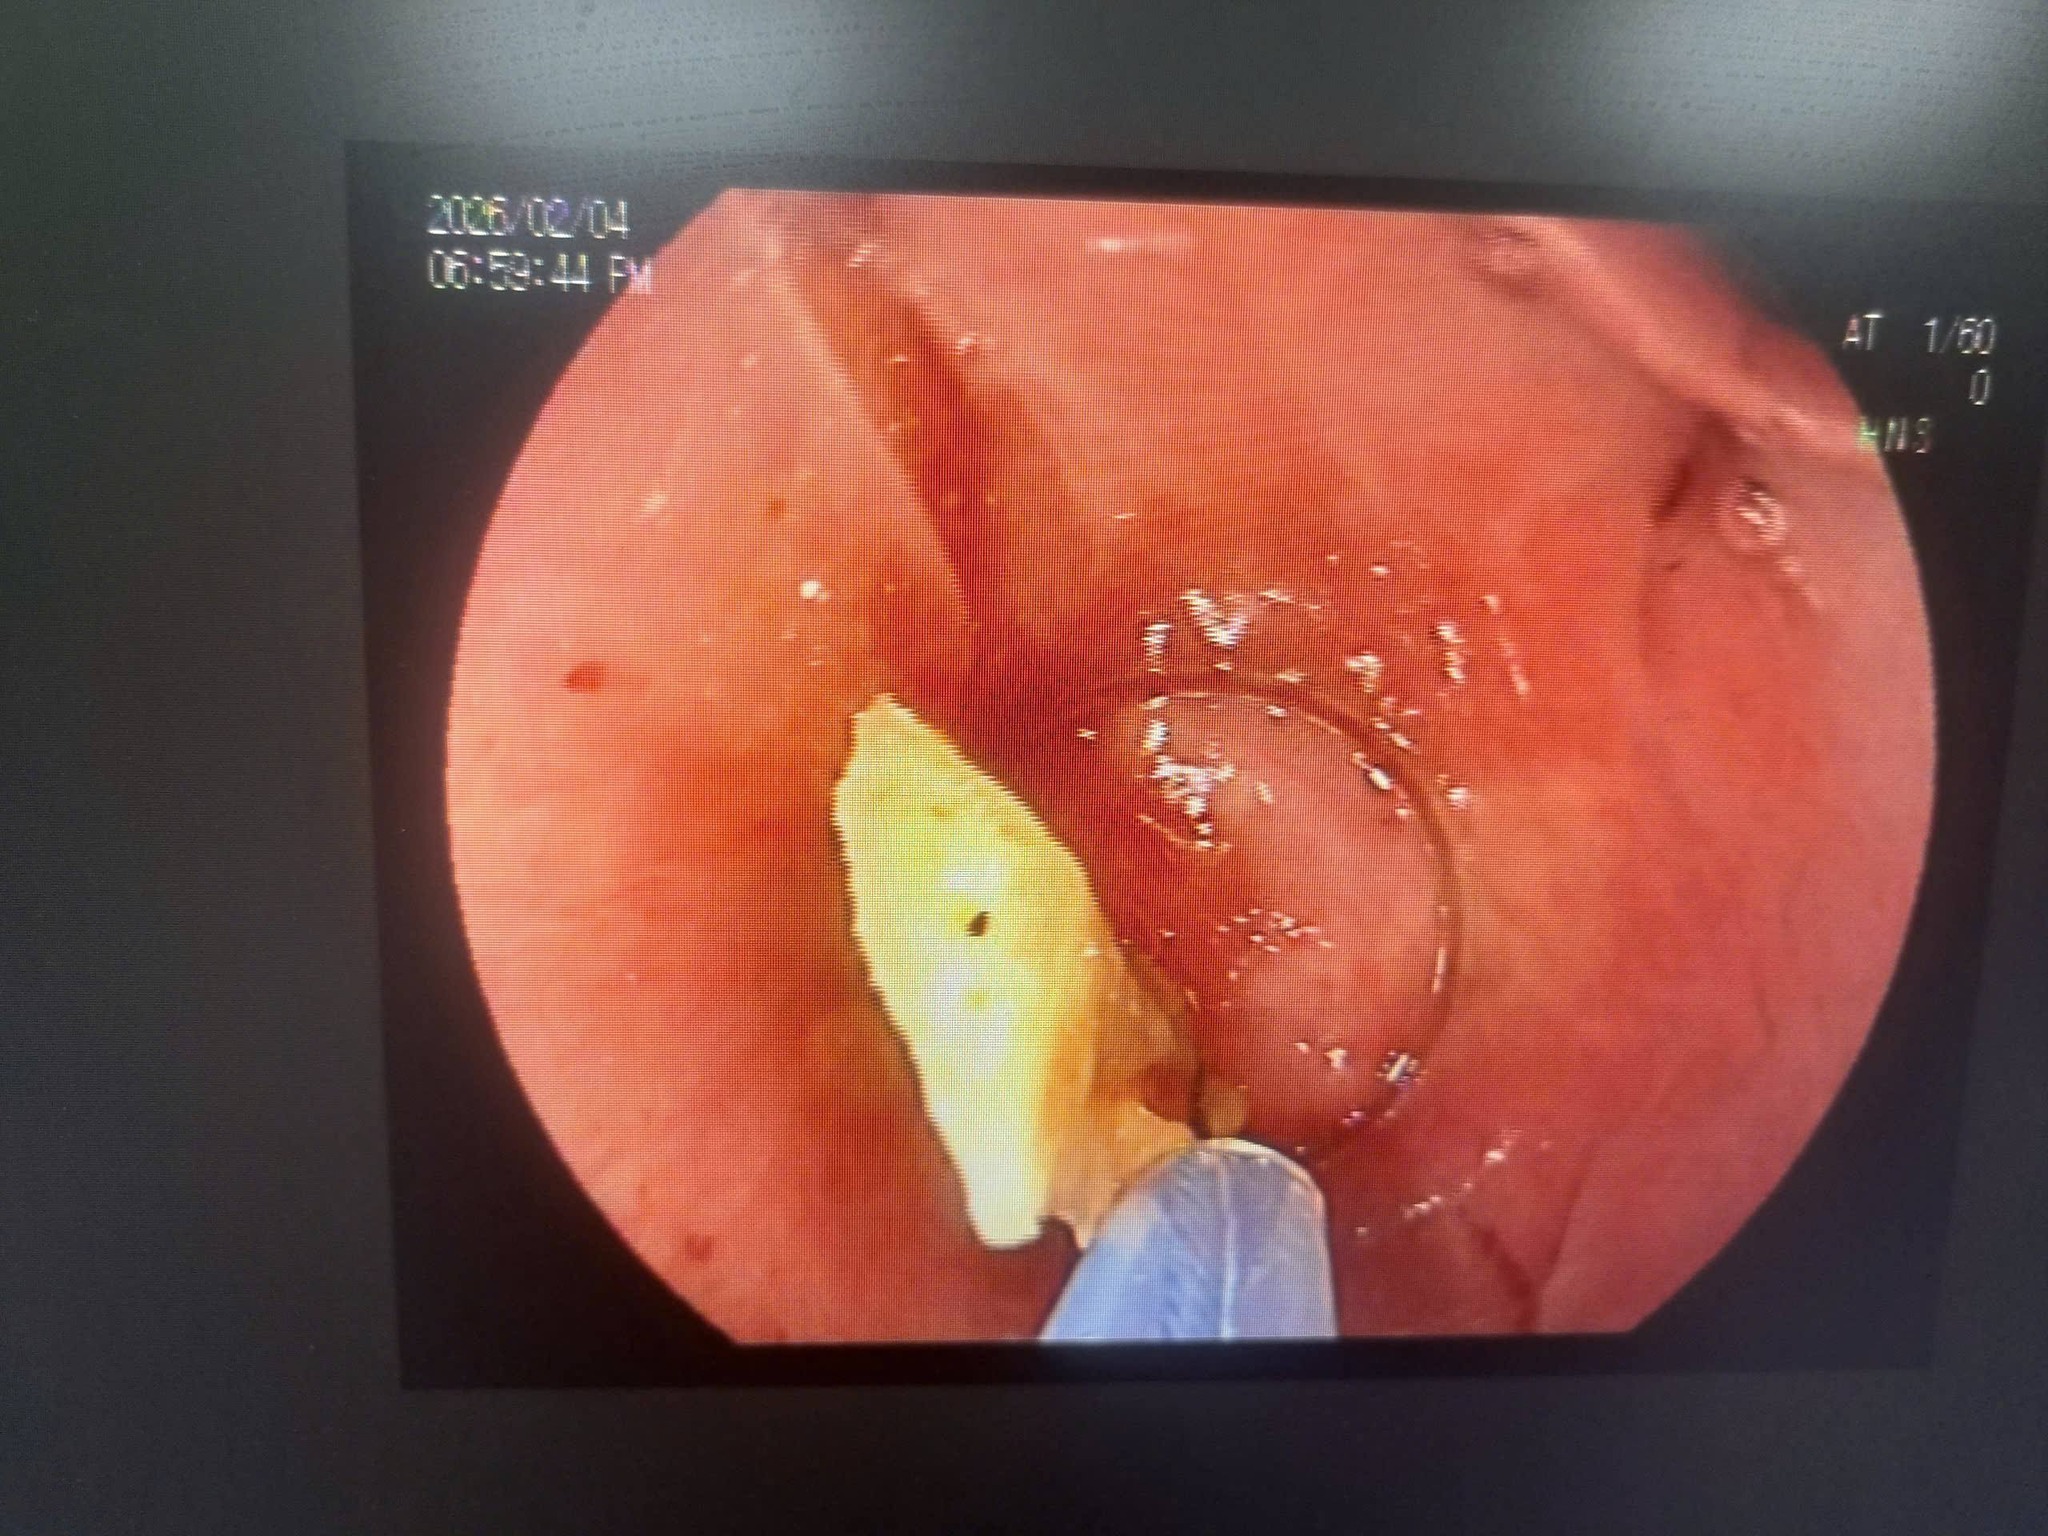

Vừa qua, các bác sĩ Khoa Tai Mũi Họng, Bệnh viện Đa khoa tỉnh Tuyên Quang đã tiến hành gắp thành công dị vật ở thực quản một bệnh nhân LXH 70 tuổi, trú tại xã Tân Trào, tỉnh Tuyên Quảng, dị vật là một miếng xương gà kích thước lớn (khoảng 2 x 4 cm), giúp bệnh nhân nhanh chóng thoát khỏi tình trạng nuốt nghẹn, khó chịu kéo dài.

Ngay sau khi tiếp nhận, các bác sĩ của khoa đã khẩn trương tiến hành thăm khám và nội soi thực quản, phát hiện một miếng xương gà lớn, sắc cạnh, mắc tại thực quản, tiềm ẩn nguy cơ gây tổn thương và biến chứng nguy hiểm nếu không xử trí sớm.

Bệnh nhân nhanh chóng được chỉ định nội soi can thiệp gắp dị vật, và dị vật đã được lấy ra an toàn, hiệu quả, không gây tổn thương nghiêm trọng cho thực quản".